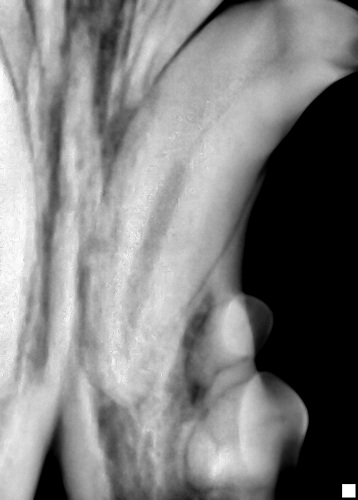

Tooth Root Abscess Kitty Presented For Swelling Ventral To Flickr

Tooth Root Abscess In Cats Vca Animal Hospital